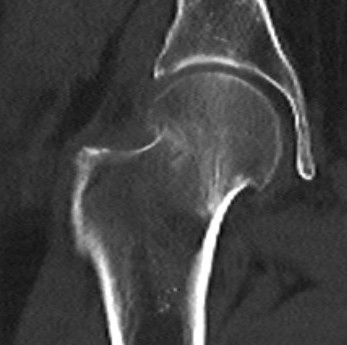

Pauwel's Classification

Based on vertical orientation of fracture line

- increased verticality / increased shear

- increased risk of noonunion / AVN

Type I: < 30° from horizontal

Type II: 30 - 50° from horizontal

Type III: > 50° from horizontal

Pauwel's type III